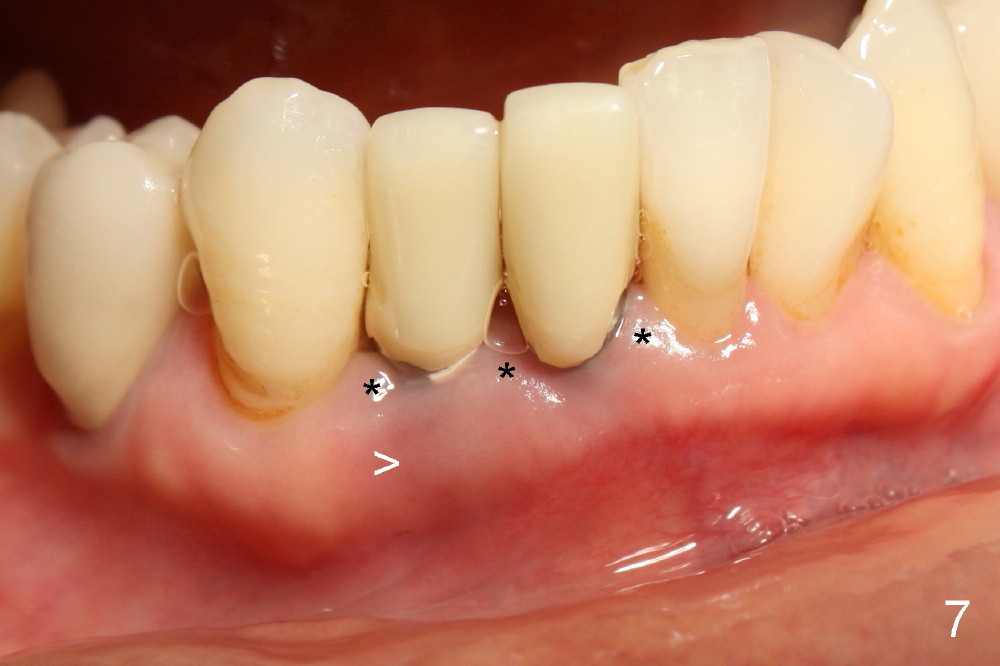

A 60-year-old lady wants to remove 2 mobile lower right incisors (Fig.1,2; with infection at the lateral (>)). Immediate 1-piece implants are placed (Fig.3,4): 3x17 mm at the central, 3.5x17 mm at the lateral. Insertion torque is > 60 Ncm for the implants. No bone graft is placed. After prep (Fig.5), two separate provisionals are fabricated (Fig.6). The one at the lateral incisor looks bulky at the cervix, because of the oversized implant for the site (over-engineering). Use of smaller implant (3.0 (instead of 3.5), 2.5 (instead of 3.0) or 2.0 mm) may solve the problem. Seven days postop, the infection resolves (Fig.7 >) with normal-looking papilla (*).